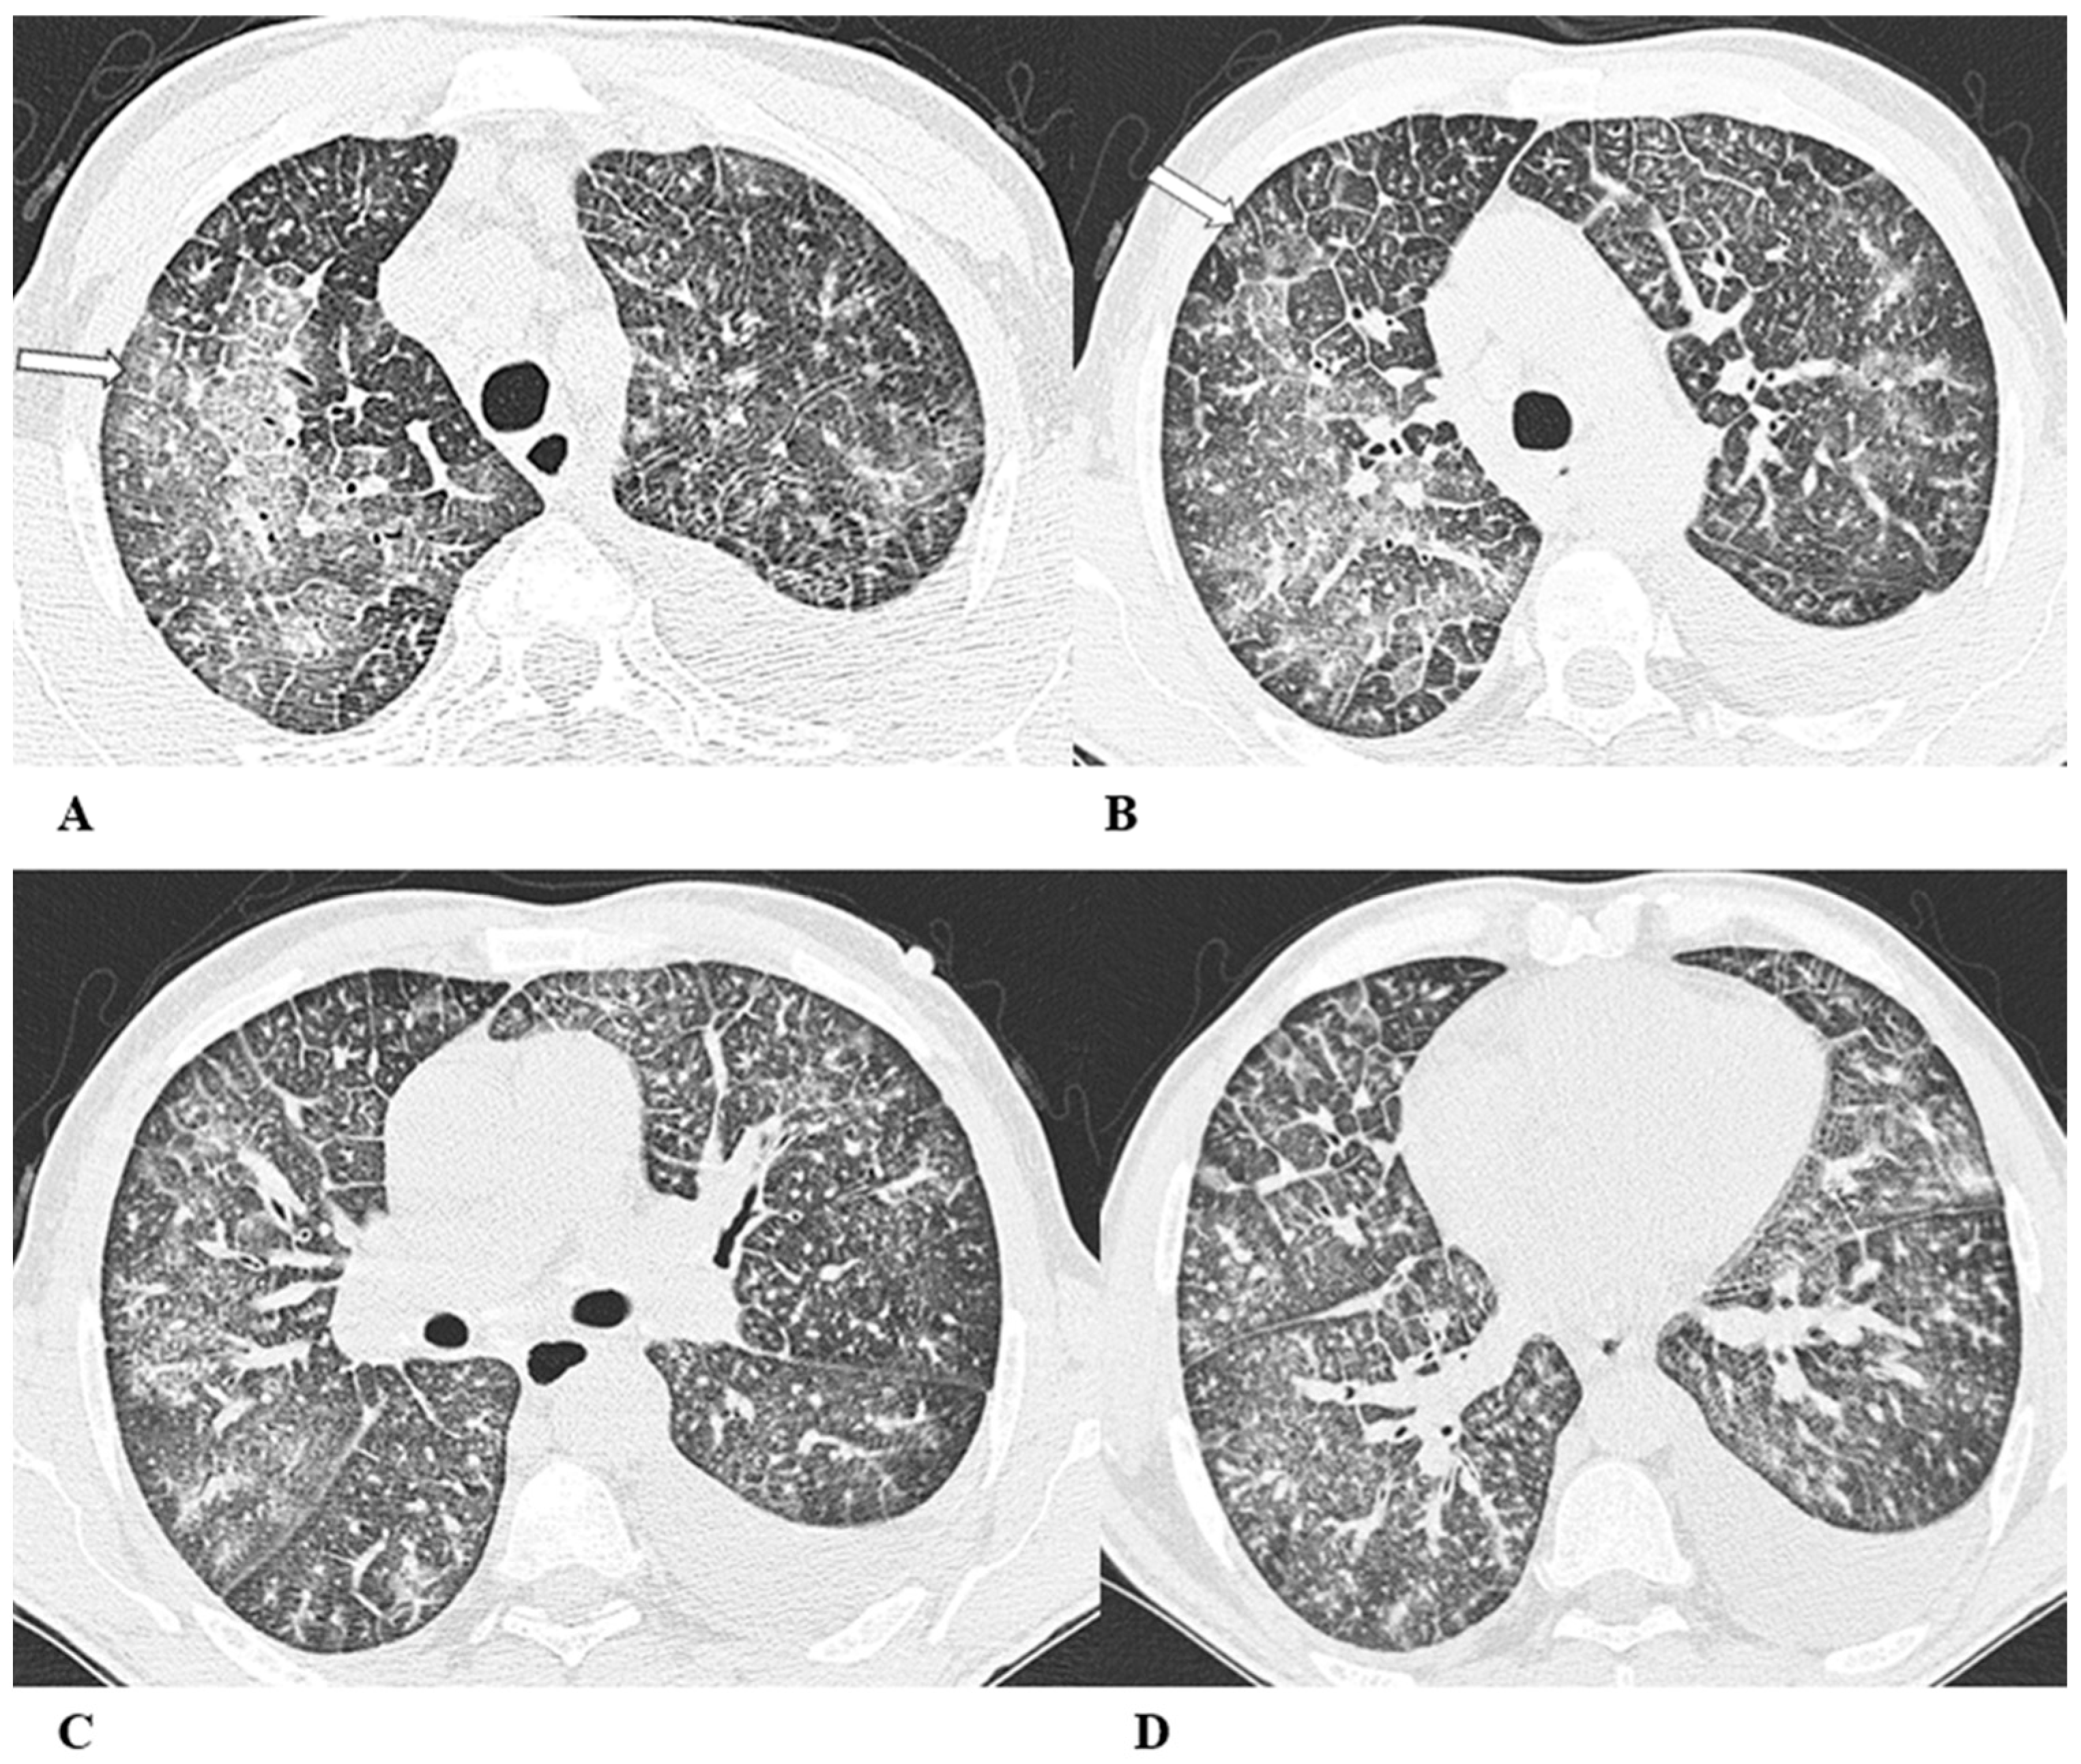

Figure 3.

Hypersensitivity pneumonia (HP). Hypersensitivity pneumonia is characterized by lymphocyte infiltrates that thicken the alveolar septa, with poorly formed non-necrotizing granulomas and multinucleated giant cells.

Typical HRCT features of acute HP are multiple bilateral small centrilobular nodules with upper lung zone predominance, lobular areas of decreased attenuation and vascularity suggestive of “air trapping” and patchy and/or diffuse GGO areas [9,12,17]. Chronic HP shows a typical “three density pattern” characterized by bilateral and diffuse lobular areas of decreased attenuation (air-trapping areas), patchy areas of real GGO in a predominant peribronchovascular distribution with traction bronchiectasis and bronchiolectasis inside (fibrosis signs), and also areas of a relative increase in density related to the normal CT appearance of the lung (GGO-like areas).

The ICI-associated HP pattern is indistinguishable from that of HP induced by allergen exposure. For this reason, in addition to the exclusion of atypical pneumonia, accurate exposure history is essential for the correct evaluation of the patient.

(A–D) A 76-year-old woman with colorectal cancer who received nivolumab and ipilimumab as second-line treatment. Seven months later, the patient presented worsening cough and dyspnea, along with weight loss, but she was able to undergo HRCT examination just two months after the onset of symptoms.

Axial chest CT scans of the upper lobes (A,B) show patchy GGO areas (black arrowheads) with over-imposed reticulation in a predominant peribronchovascular distribution and early traction bronchiectasis (black arrow).

Bilateral areas of decreased attenuation (air trapping) (white arrows) with geometric morphology are easily recognizable in both the inspiratory (A,B) and expiratory (C,D) acquisitions.